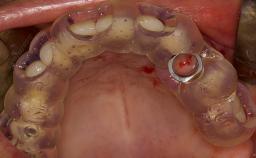

• describe the surgical treatment concept and steps for the lateral SFE technique and assess the prognosis of this procedure